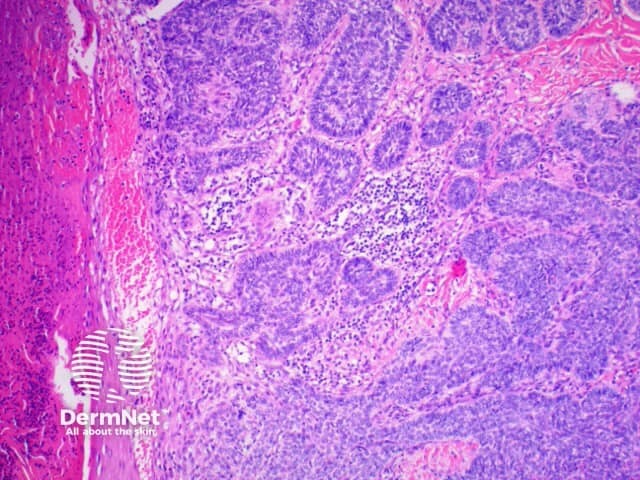

The histological features of basal cell carcinoma are typically:

Pathology of basal cell carcinoma